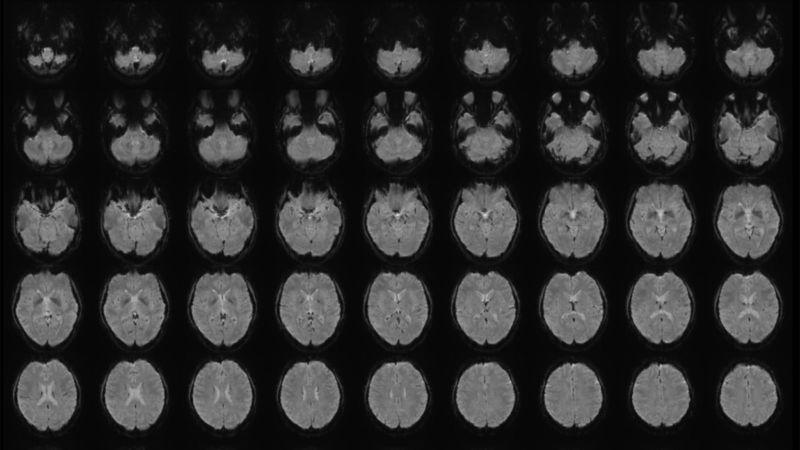

Functional magnetic resonance imaging (fMRI) is a non-invasive technique that measures brain activity. This fMRI image shows multiple horizontal views of the brain, arranged from bottom to top. Tomoyasu Horikawa